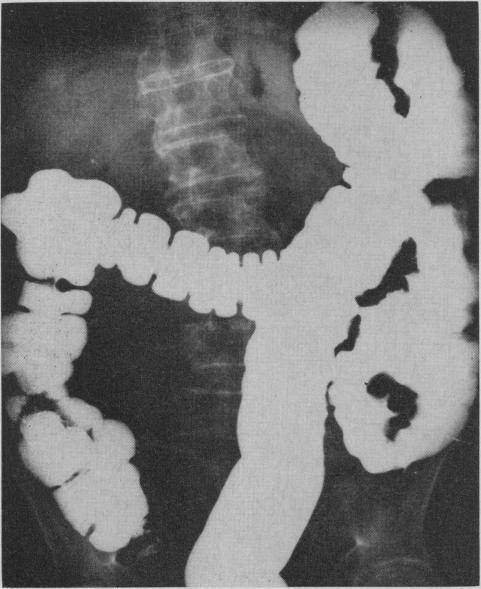

Pneumatosis cystoides intestinalis involving the left side of the colon has been infrequently described. The condition was recognized 234 years ago when it was discovered in a cadaver. It was not until 1946, however, that a description of this lesion appeared in the radiological literature of North America. Pathologically, it is characterized by the presence of subserosal or submucosal cysts, varying from one millimetre to several centimetres in diameter. The complications of this process are pneumoperitoneum and intestinal obstruction. Three patients are described, the first of whom had partial bowel obstruction. Radiolucent gas-filled cysts along the bowel wall were observed on the radiographs. An additional radiological sign noted by the authors was fixation and elongation of the sigmoid colon with loss of pliability of the bowel wall which persisted on the evacuation film.

累及结肠左侧的肠壁囊样积气症鲜有报道。该病于234年前在一具尸体中被发现时得以确认。然而,直到1946年,北美放射学文献中才出现对该病变的描述。病理上,其特征是浆膜下或黏膜下囊肿的存在,直径从1毫米到几厘米不等。该病症的并发症是气腹和肠梗阻。本文描述了3例患者,其中首例患者患有部分肠梗阻。X线片上观察到沿肠壁有透光的充气囊肿。作者注意到的另一个放射学征象是乙状结肠固定和延长,肠壁柔韧性丧失,排空片上该征象持续存在。